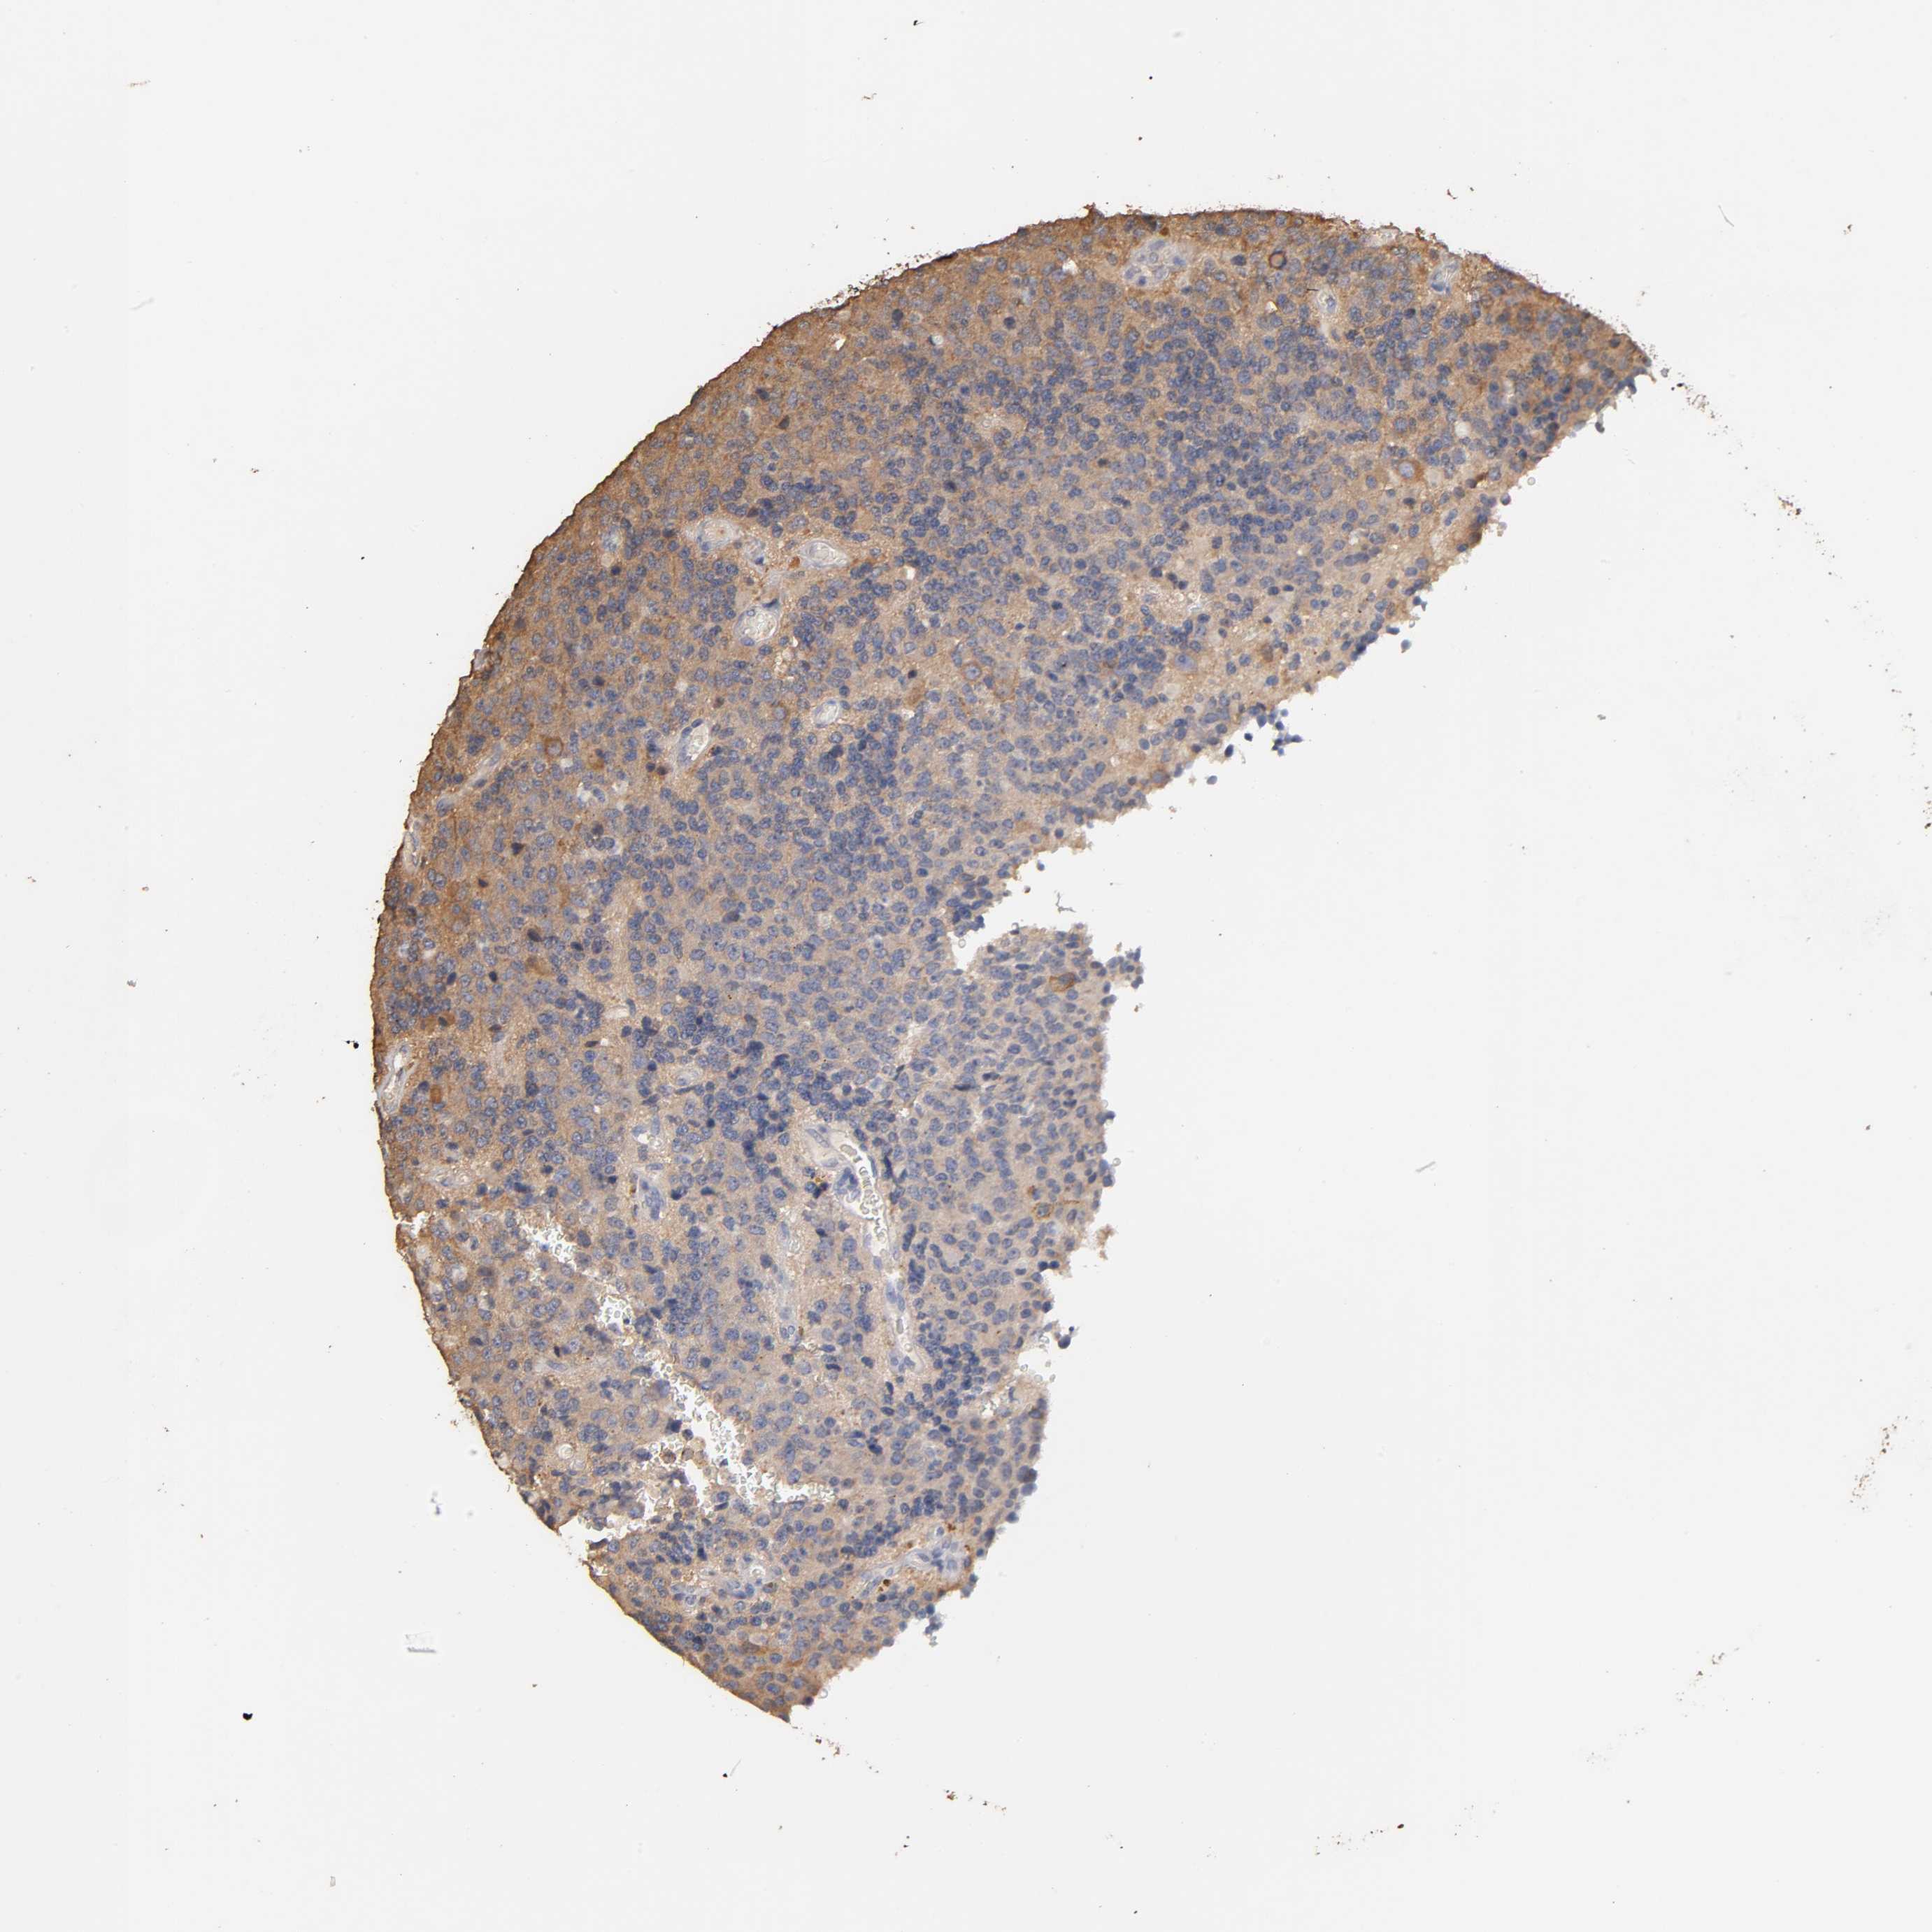

GLIOMA - Protein expressioni

A mouse-over function shows sample information and annotation data. Click on an image to view it in a full screen mode. Samples can be filtered based on level of antibody staining by selecting one or several of the following categories: high, medium, low and not detected. The assay and annotation is described here.

Note that samples used for immunohistochemistry by the Human Protein Atlas do not correspond to samples in the TCGA dataset.

Antibody stainingi

Antibody staining in the annotated cell types in the current human tissue is reported as not detected, low, medium, or high, based on conventional immunohistochemistry profiling in selected tissues. This score is based on the combination of the staining intensity and fraction of stained cells.

Each image is clickable and will lead to virtual microscopy that enables deeper exploration of all samples and also displays staining intensity scores, fraction scores and subcellular localization as well as patient and tissue information for each sample.

Antibody HPA003903

Antibody HPA072756

Antibody CAB026000

Staining

High

Medium

Low

Not detected

Intensity

Strong

Moderate

Weak

Negative

Quantity

>75%

75%-25%

<25%

None

Location

Nuclear

Cytoplasmic/membranous

Cytoplasmic/membranous,nuclear

Glioma, malignant, High grade

Glioma, malignant, NOS

Glioma, malignant, Low grade